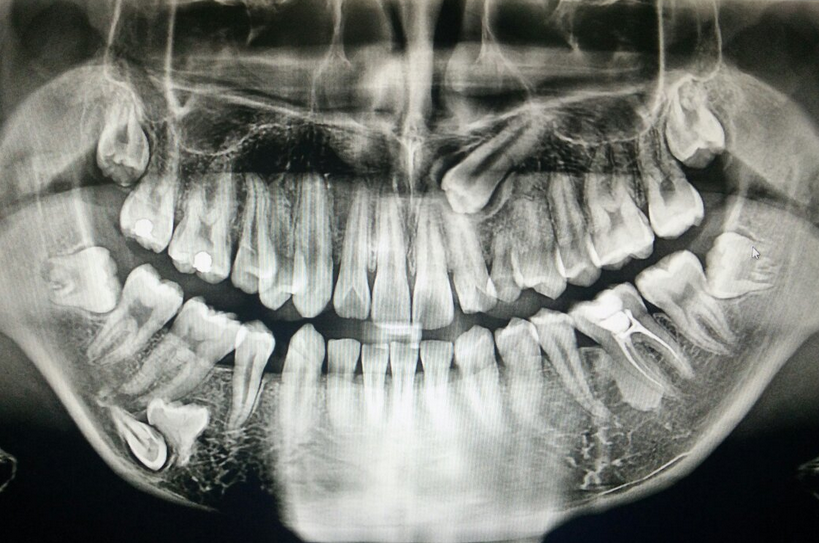

牙髓血运重建术是治疗牙髓坏死性年轻恒牙的主要治疗方法之一。牙髓血运重建治疗的关键在于控制根管内的感染以及促进根尖区干细胞的增殖分化潜能。因此在临床应用中如何选用适当的消毒药物达到既能控制年轻恒牙的感染,又能保护根尖区干细胞的目的,对治疗后促使牙根后续发育以及保存牙齿、维持牙列完整具有重要意义。

年轻恒牙发育过程中,外伤或细菌感染将导致牙髓坏死,而牙髓内的成牙本质细胞死亡会导致牙根的继续发育受阻。近年来随着组织再生技术的发展,牙髓血运重建术因其具有促进牙根增长、根管壁增厚以及根尖孔闭合等特点,成为治疗牙髓感染坏死性年轻恒牙的主要治疗方案。

牙髓血运重建术基于组织再生工程发展而来,主要通过彻底有效的根管消毒,刺激根尖出血形成以血凝块为主的天然支架并提供丰富的生长因子,为根尖乳头干细胞等种子细胞增殖和分化提供良好的微环境,并诱导其分化为成牙本质细胞和成骨细胞等,从而促使牙髓再生和牙根继续发育。有效根管消毒的同时保护根尖干细胞的活性成为牙髓血运重建术药物选择的关键考虑因素。

2021年美国牙体牙髓病学会(American Associationof Endodontists,AAE)发布的牙髓血运重建术的治疗指南中指出三联抗生素糊剂(tripleantibioticpaste,TAP)、二联抗生素糊剂(doubleantibioticpaste,DAP)以及氢氧化钙均可用于牙髓血运重建术中的根管内封药。其中TAP由环丙沙星、甲硝唑和米诺环素3种抗生素组成;DAP由环丙沙星、甲硝唑组成。此篇先阐释抗生素糊剂的抗菌特点、生物相容性和给药方式。